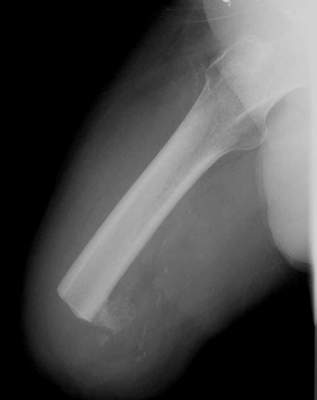

The image shown demonstrates an AKA. This is a good result and the stump is of a

length sufficient for fitting of a prosthesis.